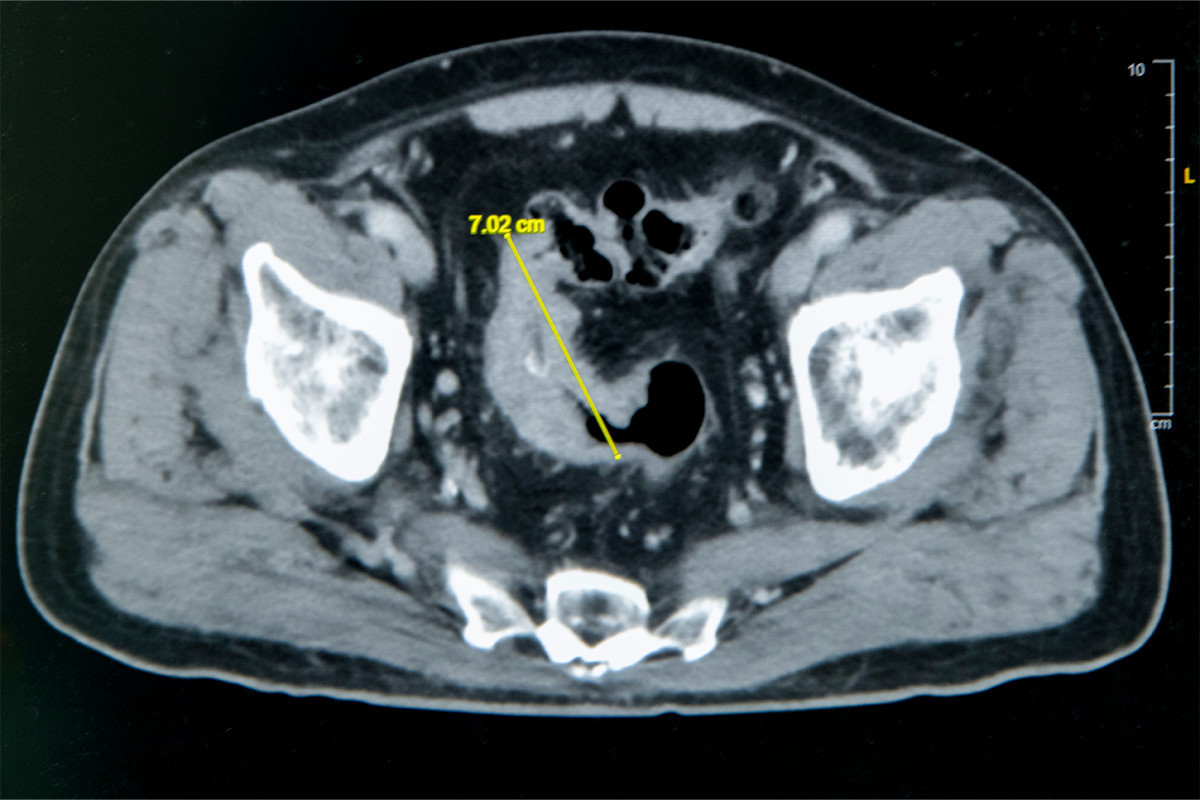

老翁罹患乙狀結腸癌,腫瘤約7公分造成腸子幾乎完全阻塞。圖/彰基醫院提供

大腸直腸外科主任張譽耀表示,老翁罹患乙狀結腸癌,腫瘤約7公分,幾乎完全阻塞腸道,導致進食後腹脹與疼痛。長期不敢進食,使體重下降、營養不良,若腸道傷口癒合不良,可能引發腸吻合滲漏甚至須製作人工肛門。經提前住院、靜脈營養補充後,患者身體狀況改善再手術,術後傷口順利癒合,疼痛低於預期,老翁驚喜表示,「沒想到這麼快就能下床,真的很感謝醫師。」